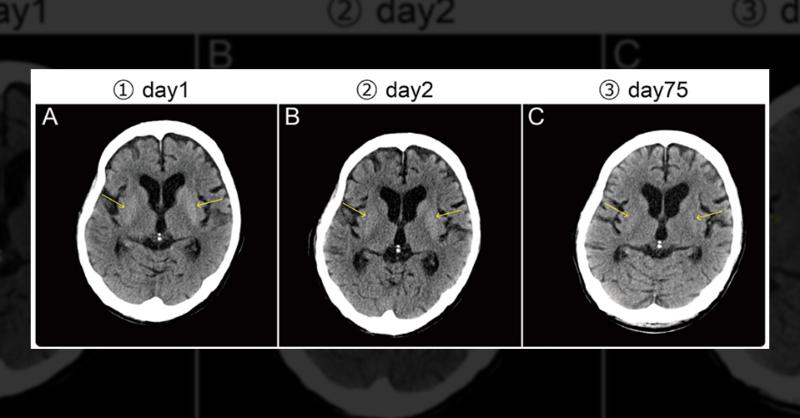

A 72-year-old male with a history of type 2 diabetes and discontinued insulin therapy presented to the ED with symptoms of severe hyperglycemia (serum glucose 841 mg/dL, HbA1c 16.3%). Despite a hypertension diagnosis, he wasn't taking antihypertensive medications. Neurological examination showed dyskinesia and slight ballism in lower limbs, but cra